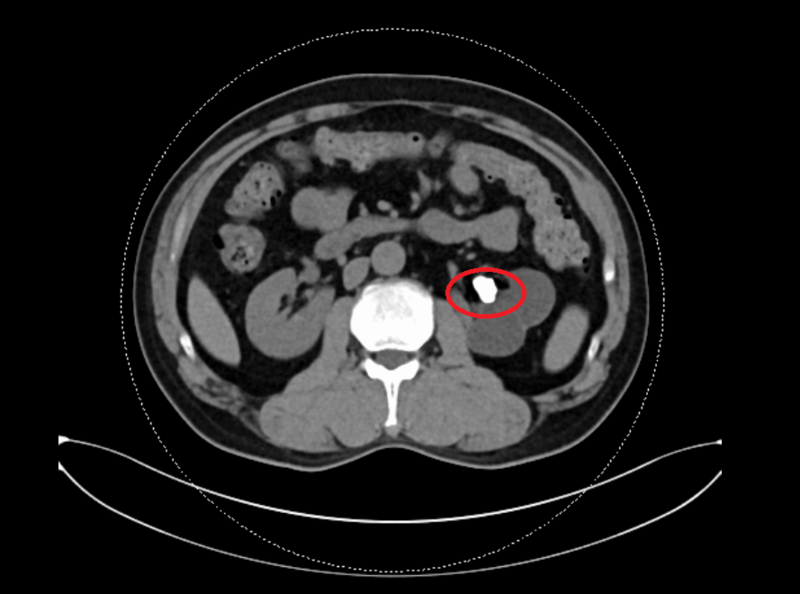

张先生术前左肾内结石

检查结果出来后,让医生有些头大,因为张先生的结石正好卡在左右肾连接的“咽喉要道”,这让手术难度直接升级!